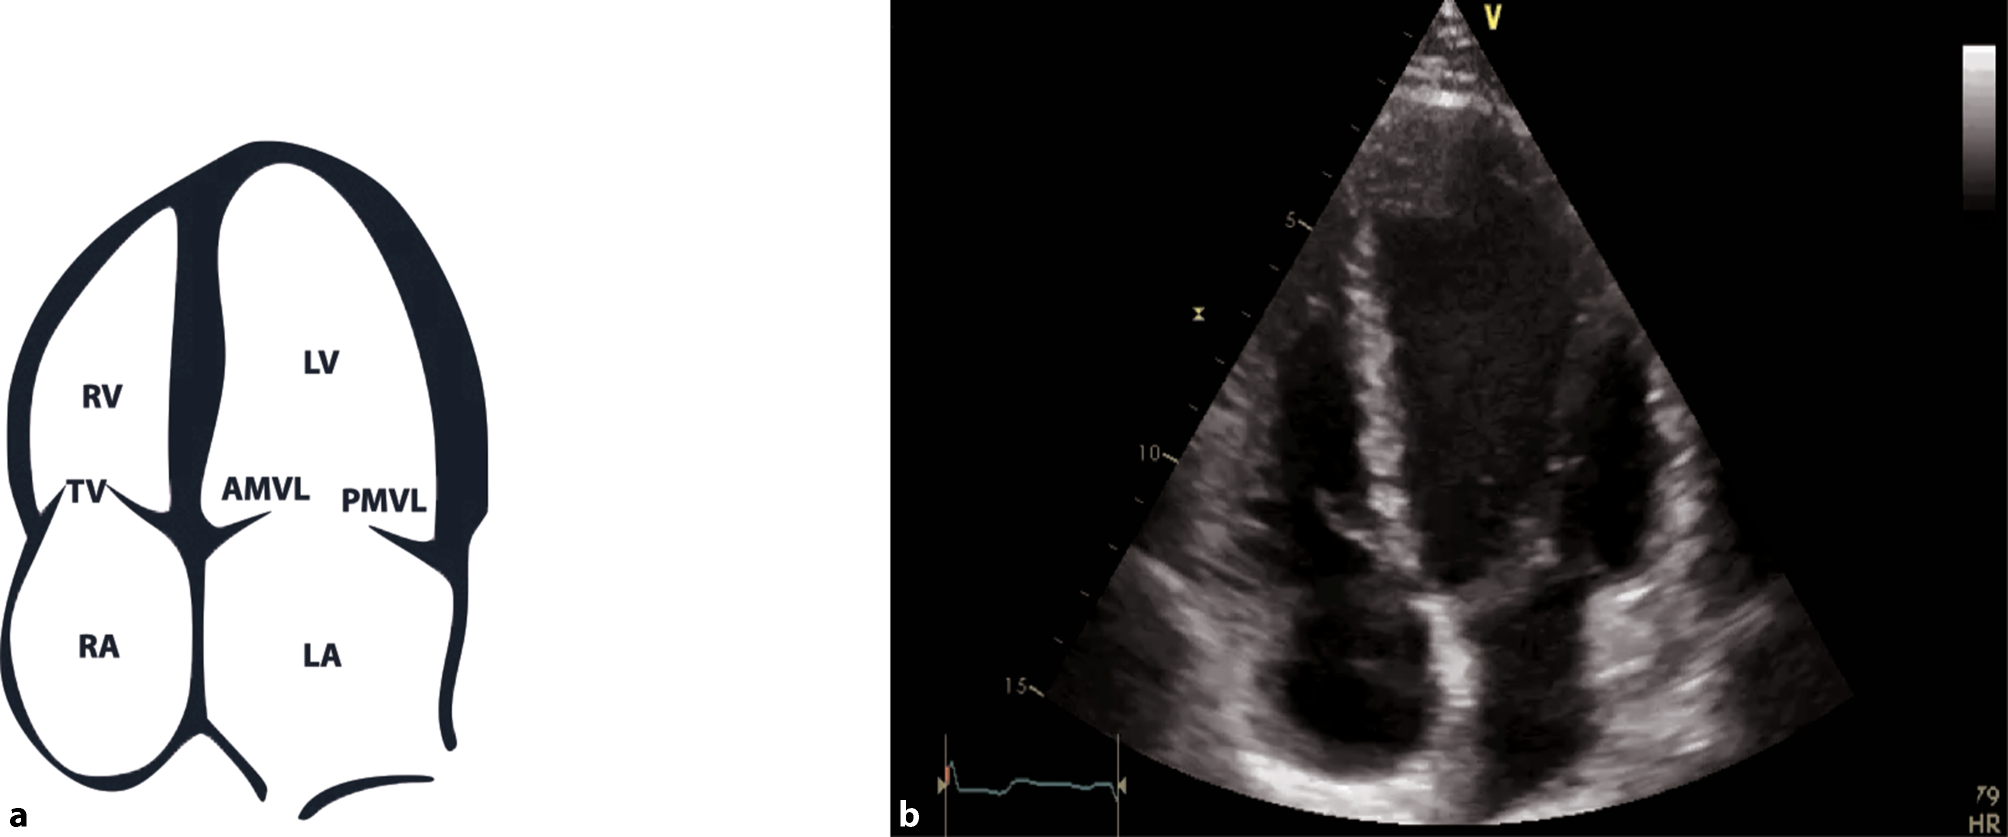

Fig. 11

Subcostal 4‑chamber view (4‑ChV). a Schematic of a subcostal 4‑ChV. RV right ventricle, RA right atrium, LV left ventricle, LA left atrium. b 2D image of a subcostal 4‑ChV

A comprehensive examination can be achieved with various views; however, in acute and intensive care settings, a subcostal 4‑chamber view (subcostal 4‑ChV) should be utilized as it provides a lot of information and is easiest to achieve in a supine patient as well. If imaging from a subcostal approach is not possible, alternative views can be chosen, such as a parasternal long axis view (PLAX) or an apical 4‑chamber view (4-ChV) (Figs. 11, 12 and 13).